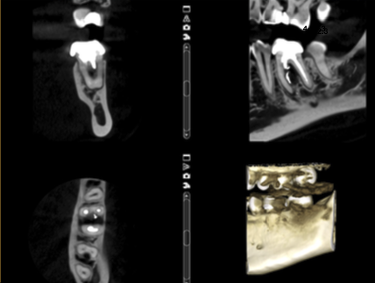

În acest caz, pacientul s-a prezentat după un abces acut în antecedente (durere puternică și spontană, cu caracter pulsatil) care a fost tratat cu antibiotice. La analiza imagisticii 3D remarcăm că există o comunicare între materialul din interiorul dintelui și spațiul dintre cele două rădăcini. Se mai evidențiază și material extrudat în acest spațiu, precum și pierdere osoasă. Deducem că este vorba de pierdere osoasă în furcație în urma cimentării unui pivot turnat. Acest pivot a fost cimentat într-un spațiu artificial creat în afara rădăcinii, această acțiune fiind un accident al tratamentului inițial (Fig. 4.12.4). Prima măsură este de a asigura izolarea cu diga dentară. Dintele prezintă o coroană artificială ce trebuie îndepărtată, diga ferește pacientul de contactul cu pulberile rezultate în urma tăierii coroanei (Fig. 4.12.5).

După îndepărtarea unui segment din pivot, vedem cavitatea artificială care traversează grosimea dintelui, până în țesutul de susținere (Fig. 4.12.8). În țesutul de susținere se observă un material albastru, gumos. Este cel mai probabil un material din clasa silicaților, folosit pentru amprentarea spațiului din interiorul dintelui pentru confecționarea pivotului metalic (Fig. 4.12.9). Reușim să îndepărtăm o parte a acestui material și închidem perforația folosind un ciment bioceramic (MTA) (Fig.4.12.10, Fig. 4.12.11).

Un astfel de tratament reușește dacă osul se regenerează iar acest proces este observabil după câteva luni. În acest caz, la radiografia de control de la 6 luni putem să remarcăm că osul este regenerat, dintele asimptomatic și funcțional (Fig. 4.12.12).